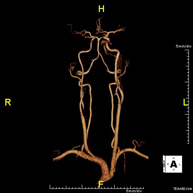

Prova diagnòstica no invasiva que consisteix en l'obtenció d'imatges d'alta definició anatòmica de les artèries cerebrals mitjançant l'ús d'un camp electromagnètic i ones de ràdio (amb un emissor i un receptor). No utilitza radiació ionitzant. En la majoria dels casos és necessari l'ús de contrast paramagnètic (Gadolini). Permet un estudi angiogràfic no invasiu gràcies a la injecció de Gadolini amb posterior reconstrucció en 2D i 3D, gràcies a estacions de treball especialitzades. Indicacions: malformacions vasculars, aneurismes d'artèries cerebrals i arteriosclerosi. - Angio-RM de Troncs supraaòrtics

Prova diagnòstica no invasiva que consisteix en l'obtenció d'imatges d'alta definició anatòmica de les artèries caròtides i vertebrals a nivell de coll mitjançant l'ús d'un camp electromagnètic i ones de ràdio (amb un emissor i un receptor). No utilitza radiació ionitzant. En la majoria dels casos és necessari l'ús de contrast paramagnètic (Gadolini). Permet un estudi angiogràfic no invasiu gràcies a la injecció de Gadolini amb posterior reconstrucció en 2D i 3D, gràcies a estacions de treball especialitzades. Indicacions: problemes circulatoris cerebrals i síncope. - Angio-RM d'Aorta Toràcica

Prova diagnòstica no invasiva que consisteix en l'estudi de l'artèria aorta abdominal per obtenir imatges d'alta definició anatòmica mitjançant l'ús d'un camp electromagnètic i ones de ràdio (amb un emissor i un receptor). És indispensable l'ús de contrast intravenós paramagnètic (Gadolini). No obstant, no utilitza radiació ionitzant. La qualitat de les imatges permet realitzar reconstruccions en 2D i 3D. Està especialment indicada en pacients amb sospita de malaltia vascular de les dues extremitats, en pacients amb malaltia vascular de les dues extremitats com a mapa vascular abans del tractament (percutani o quirúrgic), com a mapa vascular prequirúrgic en pacients amb lesions òssies o musculars que requereixin cirurgia, etc. - Angio-RM Lesió de parts toves

Prova diagnòstica no invasiva que consisteix en l'estudi de les artèries de la cintura escapular, el braç, l'avantbraç i la mà per obtenir imatges d'alta definició anatòmica mitjançant l'ús d'un camp electromagnètic i ones de ràdio (amb un emissor i un receptor). És indispensable l'ús de contrast intravenós paramagnètic (Gadolini). No obstant, no utilitza radiació ionitzant. La qualitat de les imatges permet realitzar reconstruccions en 2D i 3D. Està especialment indicada en pacients amb sospita de malaltia vascular de les dues extremitats, en pacients amb malaltia vascular de les dues extremitats com a mapa vascular abans del tractament (percutani o quirúrgic), com a mapa vascular prequirúrgic en pacients amb lesions òssies o musculars que requereixin cirurgia, etc.